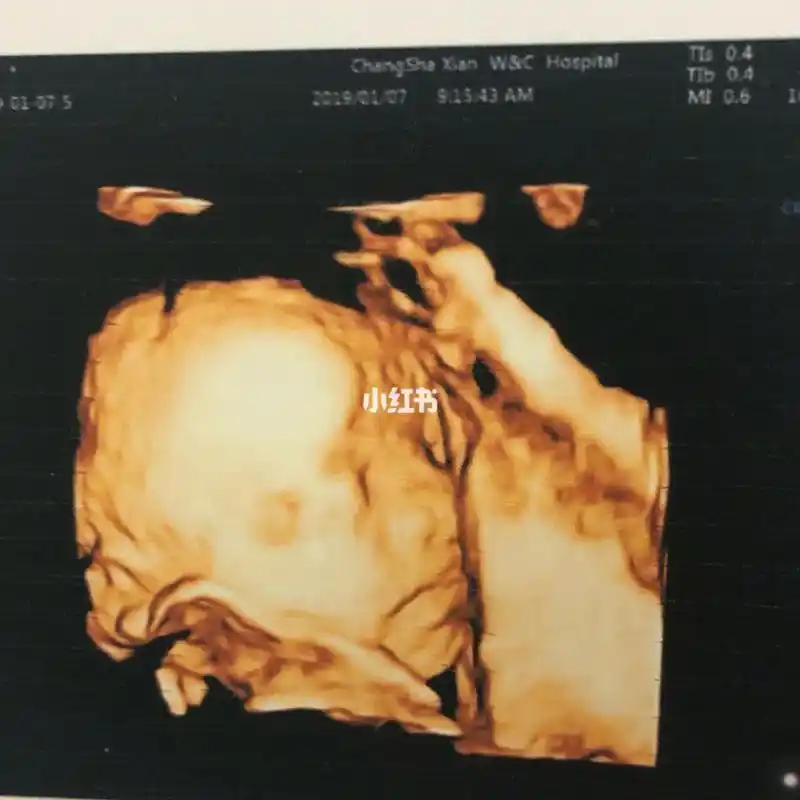

24周4天!第一次四维清楚看到宝宝的脸,纪念一下